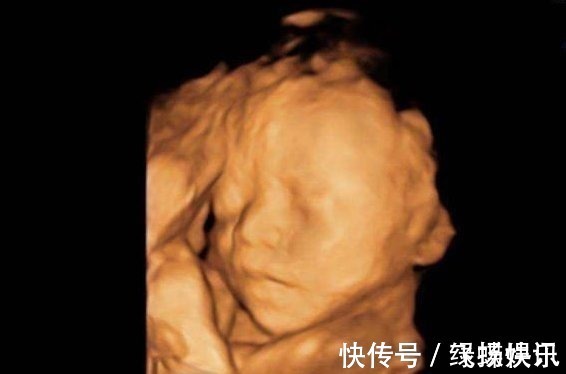

对于孕妈们来说,怀孕的时候去医院做检查是一件非常惊心动魄的事情,生怕宝宝在自己肚子里长得不好。现在医院里医生观察胎儿的生长状况有很多医疗手段,像二维、三维、四维彩超,通过这些手段观察胎儿在母亲肚子里的发育情况。通常孕妈们都会认为四维彩超是最好的检查手段,因为能看到宝宝的动态。而事实真的是大家认为的这样吗?孕妈做“四维”前,这3件事最好要提前了解,不然可能就是白花钱。这里简单介绍一下关于四维彩超的三件事,希望孕妈们能提前了解一下,不要花了冤枉钱。

四维彩超和其他彩超有什么不同之处呢?四维彩超其实是让三维彩超“动起来”,让孕妈和医生能看到宝宝动起来的样子。不管是二维彩超还是三维彩超,医生用的检查机器都是一样的,只是后期用了特殊的软件。所以了解完这个本质后,孕妈们可以基于这个好好考虑一下做这种检查的次数了。